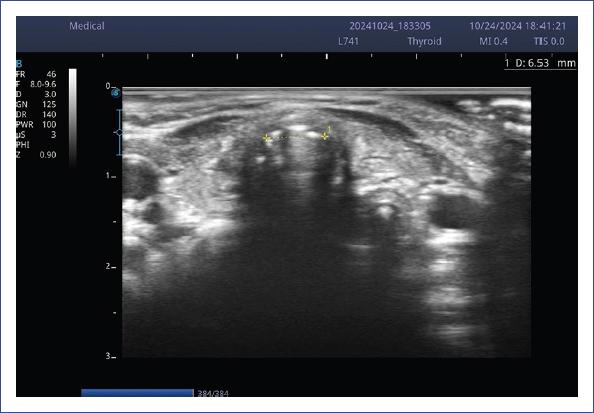

El IPFS y el LACWD se midieron con ultrasonido portátil Sonoscape E2 y transductor lineal (7-15 mHz) usando una configuración para tejidos blandos. Dicha medición se realizó por un intensivista pediatra ecografista crítico durante el protocolo de retiro del ventilador. Se obtuvieron tres mediciones y se promediaron. Las estructuras que se visualizan en la ecografía laríngea se muestran en la figura 1. La técnica de medición del IPFS se explica en la figura 2, y la medición del LACWD se explica en las figuras 3 y 4.

Figura 1 Estructuras anatómicas en la ecografía laríngea. AC: arteria carótida; CC: cartílago cricoides; E: esófago; ECM: esternocleidomastoideo; MP: músculo platisma; VA: vía aérea; OHM: músculo omohioideo.